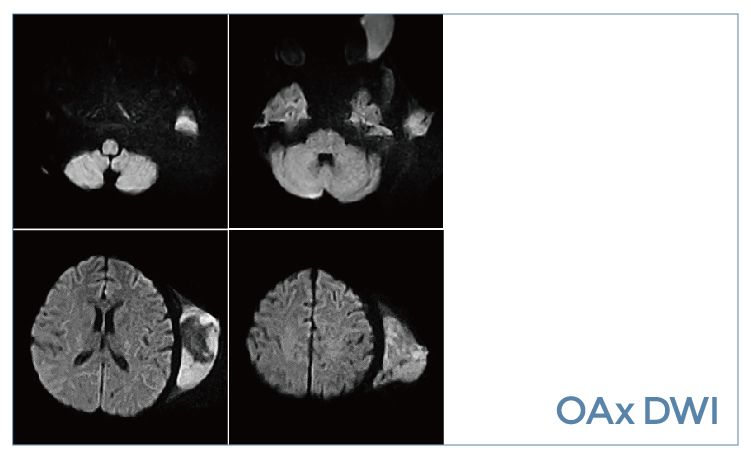

【朗润影像档案】磁共振影像病例分享(编号20190920)